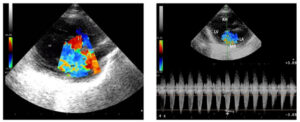

↑ 上の写真は、猫の僧帽弁閉鎖不全症の心エコー図です。

■ モザイク色の部分は、本来一方通行の血流が『逆流』になっている状態です。

• 心エコー検査     :  僧帽弁(左の心臓の房室弁)の逆流を確認